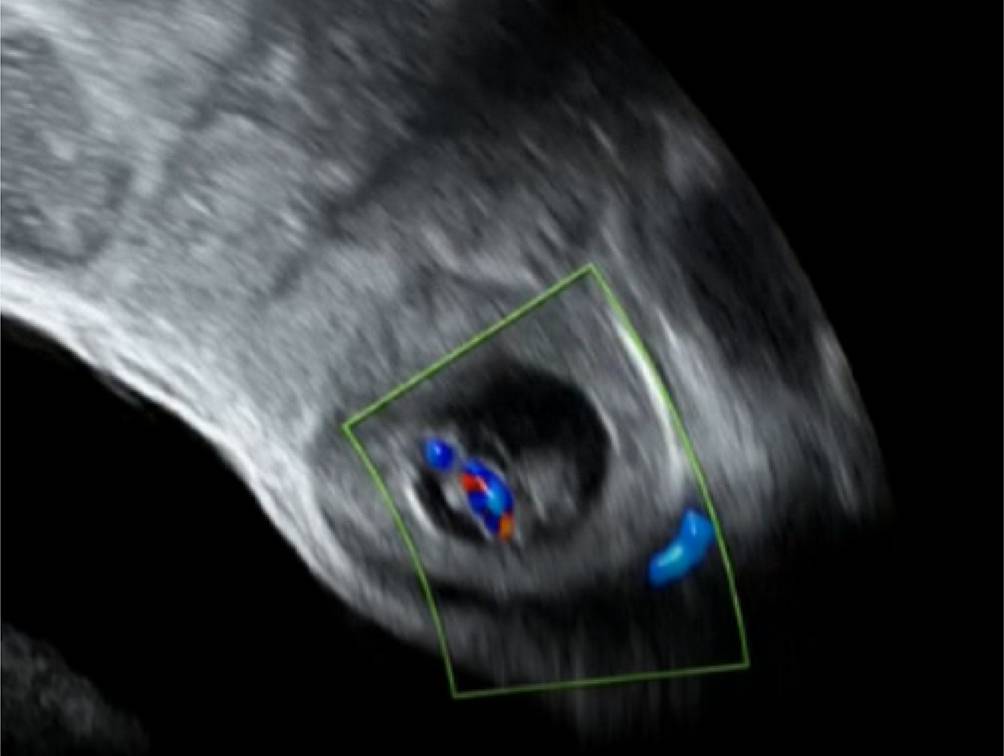

Die Diagnose einer ektopen Schwangerschaft besteht in der eindeutigen Darstellung einer extrauterinen Struktur im Adnexbereich. Dies gelingt am ehesten, wenn die Schwangerschaft schon weiter fortgeschritten ist, man einen leeren Uterus und daneben einen Fruchtsack, vielleicht sogar mit Dottersack und Embryo, im Vaginalschall darstellen kann (Abb. 1). Man wird eine Woche nach Ausfall der Regelblutung nicht abwarten, bis sich in den nächsten Wochen das Vollbild der EUG entwickeln kann, sondern wird bei der Diagnose PUL nach diskreteren Hinweiszeichen fahnden, vornehmlich dem Klecks („blob sign“) und dem „bagel“ [2].

Abb. 1

Eine vitale ektope Schwangerschaft (EUG) liegt der deutlich gefüllten maternalen Harnblase an. Derartige „klassische“ Ultraschallbefunde sind heute selten geworden